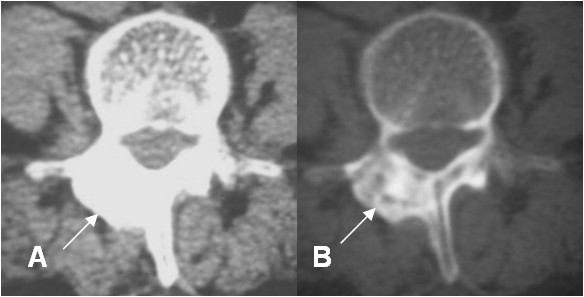

Fig 67 B. Osteoblastoma.

A: TAC axial en ventana de tejido y B: en ventana ósea. Lesión expansiva y esclerótica, en la lámina derecha de la vértebra, sin ruptura de la cortical, que corresponde a osteoblastoma.